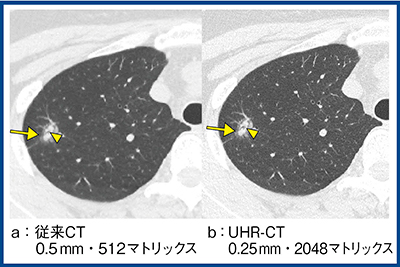

図1はびまん性汎細気管支炎であるが,従来CT(a)と比較し,超高精細CT(b)では,すりガラス状陰影などの境界や陰影内部の細気管支の構造物が明瞭である。また,超高精細CTでは,高周波成分を強制的に強調する必要がないため,結節周囲のアンダーシュート(図1↑)が低減されている。

図1 びまん性汎細気管支炎における画像比較

図4は肺腺癌であるが,従来CT(a)と比較して,超高精細CTの最高空間分解能(画像スライス厚0.25mm・2048マトリックス)の画像(b)では,結節内の細気管支透亮像(◀)や,すりガラス状陰影(→)の内部のテクスチャが明瞭である。

図4 最高分解能の画像の有用性(肺腺癌)